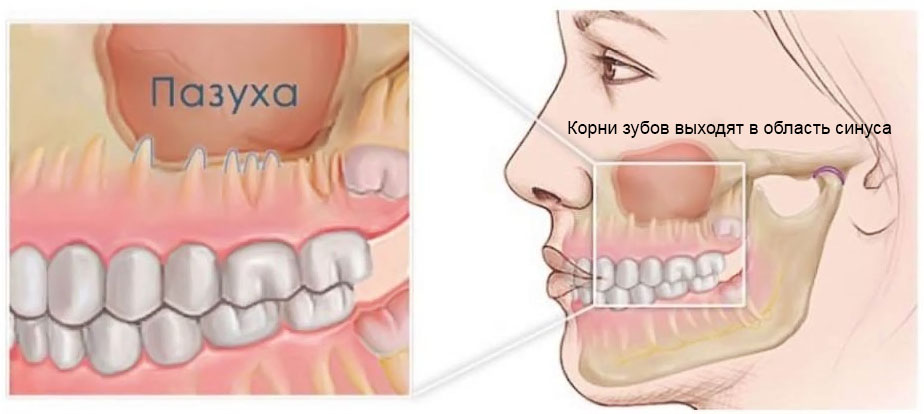

Реплантация зуба: Этапы и особенности операции